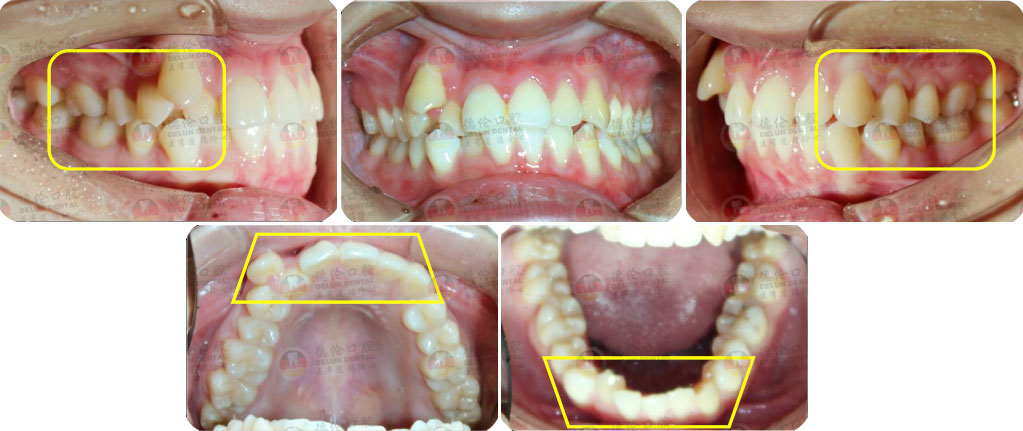

骨性I類,均角,安氏I類

上牙列重度擁擠,下牙列輕-中度擁擠

上中線右偏

13唇側錯位

• 【治療方案】

拔除14,排齊上牙列

下頜尖牙適當擴弓,配合適量鄰面去釉,排齊下牙列

上頜左側配合適量鄰面去釉,調整中線

盡量調整后牙為尖窩咬合關系

矯治前后對比

蛻變周期:上頜16個月,矯治效率提升30%,下頜12個月,矯治效率提升20%